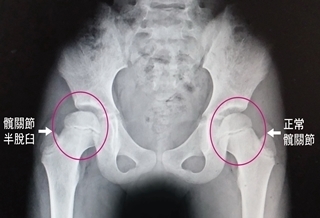

走路像鴨子 竟是髖關節脫臼

(優活健康網記者徐平/綜合報導)一名初學滑直排輪的8歲女童,屢屢摔倒,一直感覺右邊腹股溝疼痛,後來走路出現一跛一跛情況,就醫後經X光檢查發現,該女童的右側髖關節半脫臼,醫師提醒,髖關節半脫臼如未妥善治療,有可能會導致脊椎側彎或走路外八字的嚴重後果。假性長短腳 右腳有些微較短澄清醫院中港院區復健科主治醫師董莉貞表示,經髖關節外展理學檢查發現女學童的右側腹股溝部位有疼痛現象,而兩腳已出現假性長短腳,右腳有些微較短,強烈懷疑是髖關節的問題。做X光檢查,證實是右側髖關節半脫臼,從影像可以看出她的股骨頭有部分跑出髖臼之外,才造成腹股溝疼痛及假性長短腳現象,由於病情並不嚴重,建議立即進行復健治療。徒手進行髖關節展延並加強臀肌力量復健治療部主任蔡永裕指出,由於該女童的髖關節半脫臼導致關節活動角度受限,是一跛一跛走進復健治療部,經短波治療儀增加關節的延展性,再徒手進行髖關節展延運動並加強臀肌力量,讓半脫臼的髖關節即早恢復到原來的活動度,經持續2週復健治療,該女童已恢復正常走路姿態。臀部橫向皺痕不對稱 即早求醫孩童罹患髖關節半脫臼並不容易,除了先天性外,有可能因經常性的撞擊所造成,如果未接受妥善的復健治療,可能會導致脊椎側彎、跛行,董莉貞醫師強調,至於先天性的髖關節半脫臼,家長要細心觀察,如發現小孩兩側臀部橫向皺痕不對稱、長短腳、走起路來外八字像鴨子走路一樣,就要即早求醫,接受最適當的治療。